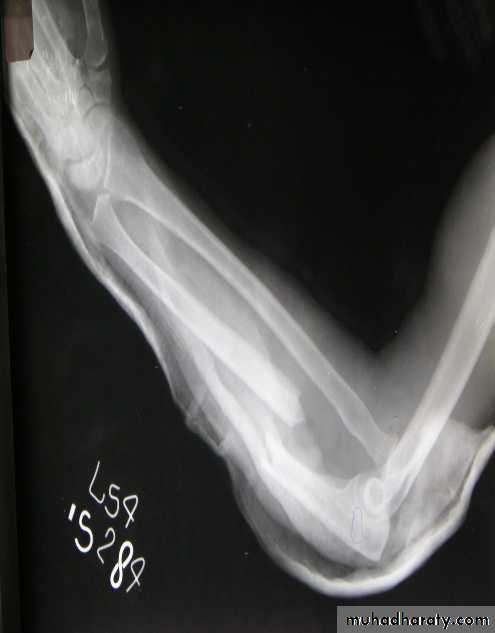

HoldI. Continuous traction

1.Traction by the gravity.

For upper limb injure.

2.Skin traction:

Not more (4-5KG) e.g.

fracture in children.

3.Skeletal traction:

By stein Mann pin or

Denham pin.

>5KG.

4.Fixed traction:

In Thomas splint.5.Balanced traction

Over pulleys.6.Combined traction.